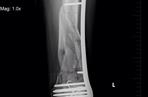

Dramat polskiej Angeliny Jolie, czyli Agnieszki Orzechowskiej (34 l.), trwa trzeci rok. Po wypadku, podczas którego wyleciała z okna, przeszła już kilka skomplikowanych operacji połamanych nóg. Teraz modelka żyje ze śrubami w kończynach. Ale to nie koniec jej męki. Wkrótce czeka ją bolesny zabieg ich usunięcia i kolejnego zamontowania. - To jak rzeź - płacze Orzechowska.

Nie wygląda na to, żeby cierpienie celebrytki wkrótce miało się zakończyć. W najbliższych tygodniach przejdzie aż cztery operacje, podczas których zamontowane w jednej z nóg śruby zostaną usunięte, a następnie ponownie zamontowane. Oznacza to, że modelka ponownie trafi na wózek inwalidzki, a wielomiesięczna rehabilitacja rozpocznie się na nowo. Na samą myśl o tym Agnieszka płacze z przerażenia.

- Okazało się, że mam problem z chodzeniem. Dlatego muszę ponownie przejść operację. Kości stopy i śródstopia źle się zrosły. Śruby z kolana i uda muszą być wyrwane. Jedna z nich przebija mi skórę. To bardzo boli. Boję się. Znów nie będę mogła chodzić, wyląduję na wózku. Znowu mnie potną. To jest jak rzeź - płacze Orzechowska. Termin operacji nie jest jeszcze znany. W związku z tym modelka stara się jak najwięcej pracować. Wszak potem będzie wyłączona z życia zawodowego. Już niedługo zobaczymy ją w roli niani w programie telewizji TTV.